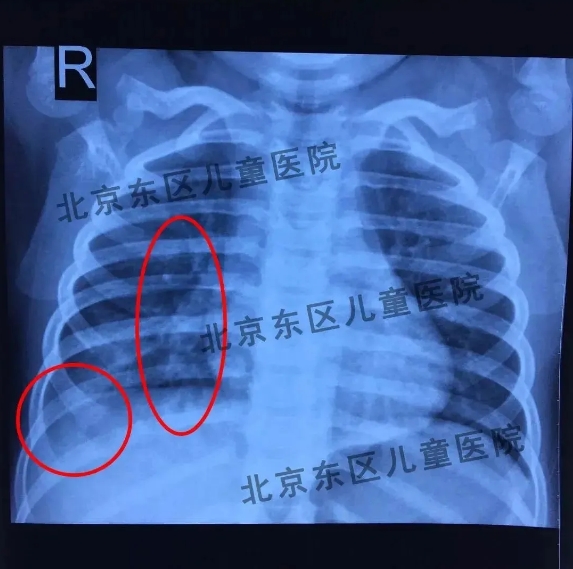

王硕主任强调,在临床诊断中,肺炎要听更要看!胸部症状早期可能不明显,仅为呼吸声粗糙或呼吸声音稍减低,随之,可能听见固定的中、细湿啰音或捻发音,通常是在哭闹、深呼吸时才能听到,在背部两侧下方及脊柱两旁较多,儿童深吸气末更明显,叩诊正常或有轻微的叩诊浊音、减低的呼吸音,但当肺炎的范围扩大到整个肺叶时,肺里可能充满了炎症和渗出,如果发现一侧肺有明显叩诊浊音或呼吸音降低,就应考虑是否出现胸腔积液渗出或肺不张的情况。所以,重点来了,单纯靠听诊或抽血是不能完全诊断的,在高度怀疑儿童患有肺炎的时候建议拍摄胸片,因为儿童患有肺炎以后胸片有高密度的斑片影,这对于肺炎的诊断很有帮助。儿童拍摄胸片的时候放射量非常小,并且拍摄的时候曝光时间特别短暂,对于儿童机体的影响可以忽略不计,家长无需过度担心。

肺炎胸片:胸片中可以看到云絮状阴影